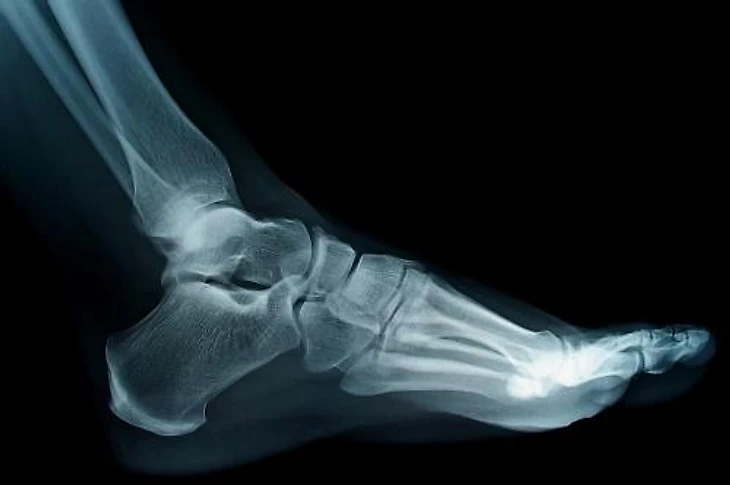

Рентгенография поможет выявить структурные костные изменения, такие как пяточные шпоры, артроз или переломы.

У взрослых пятка состоит из одной кости, называемой пяточной костью, а у детей дошкольного возраста она сформирована из нескольких костных сегментов, соединенных хрящами. Чтобы в процессе развития организма не возникало проблем с опорно-двигательной системой, важно выбирать правильную обувь. Не «на вырост» или «разносятся», а строго по размеру и ширине стопы, особенно это касается обуви для бега.